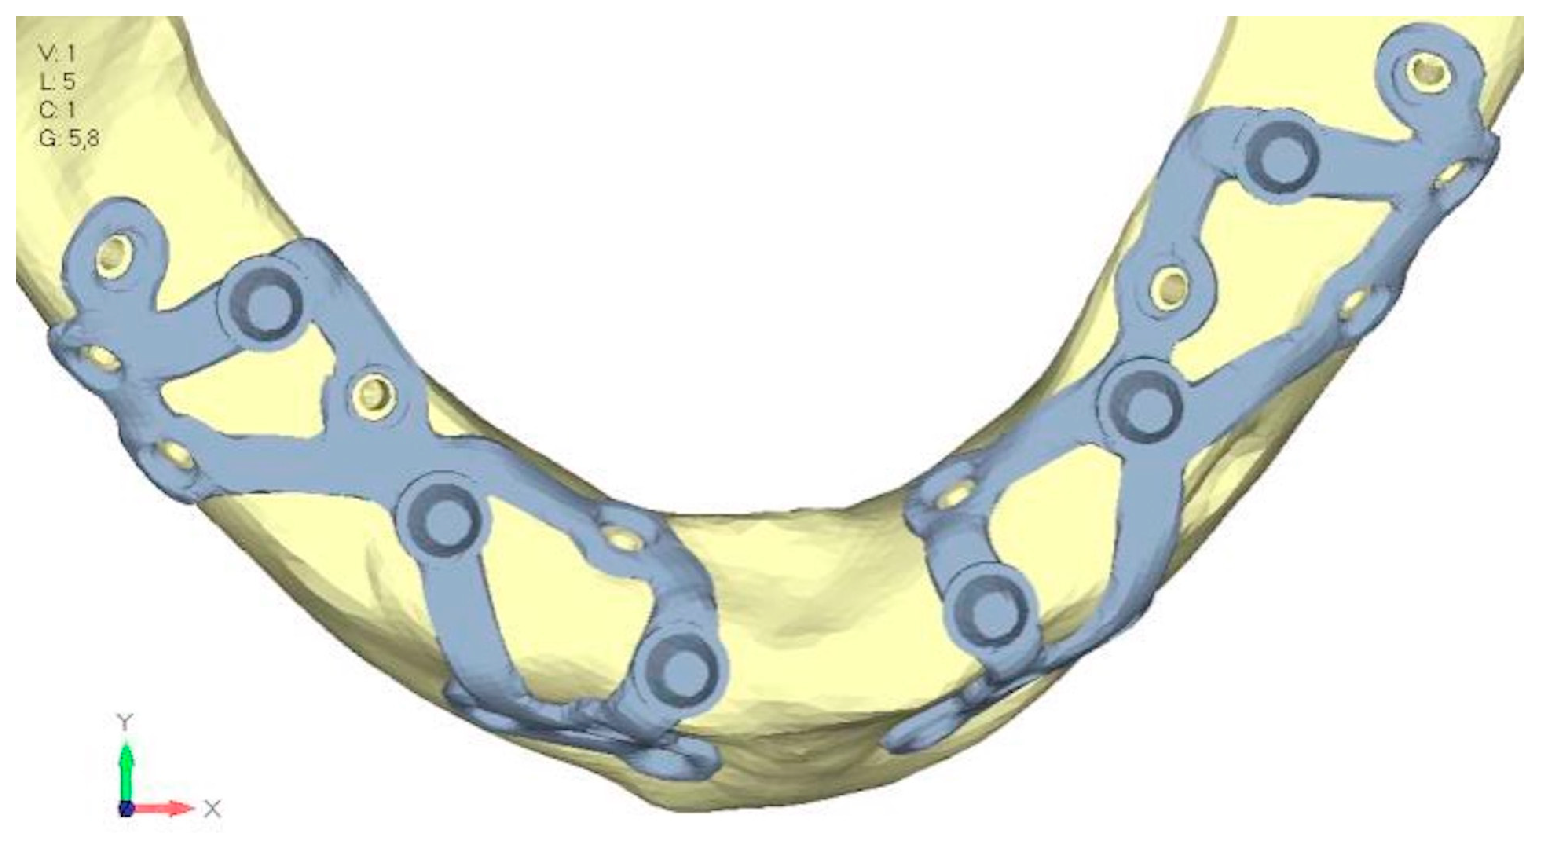

- Model V4. This version was derived from version 3 by adding a screw in the posterior sector, positioned in the vestibular direction (Figure 29). Again, the addition of an anchoring screw has allowed for more effective distribution of the stresses. The posterior alveolar area, particularly around the more posterior screws, remains notably stressed (Figure 30a,b). However, this phenomenon is attributed to the geometry and configuration of the bone rather than the presence of a cortical screw.